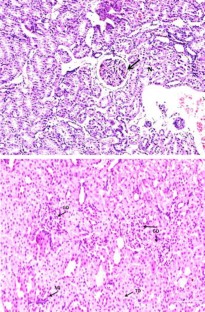

We investigated the effects of sildenafil citrate (SC) on podocyturia in N ω-nitro-l-arginine methyl ester hydrochloride (l-NAME) model of pre-eclampsia (PE). One hundred and twenty Sprague–Dawley rats (SDR) were divided into five groups like pregnant control (PC), early-onset PE (EOPE), late-onset PE(LOPE), early and late-onset PE with SC-treated groups [EOPE (SC); LOPE (SC)]. PE was induced in SDR by oral administration of l-NAME in drinking water for 4–8 days for EOPE and 8–14 day for LOPE. The blood pressure, urine volume and total urine protein were increased in EOPE and LOPE groups when compared to PC, and all the above parameters decreased in EOPE (SC) and LOPE (SC) groups when compared to EOPE and LOPE groups, respectively. The EOPE and LOPE groups showed an increase in urinary nephrin mRNA and podocin mRNA levels compared to PC group. Increases in serum and renal soluble fms-like tyrosine kinase-1 (sFlt-1) expression levels and decreases in renal vascular endothelial growth factor (VEGF) expression and serum placenta growth factor (PlGF) levels were observed in EOPE and LOPE groups when compared to PC group. In addition, decreases in serum and renal sFlt-1 expression levels and increases in renal VEGF expression and serum PlGF levels were observed in EOPE (SC) and LOPE (SC) groups when compared to EOPE and LOPE groups, respectively. The light microscopy showed that the renal tissue of l-NAME-treated rats had extensive glomerular damage, tubular damage and infiltration by mononuclear cells when compared to PC group. Therefore, SC ameliorated podocyturia through its effects on the antiangiogenic/angiogenic status in this animal model.

Fig. 1

Fig. 2

Fig. 3

Fig. 4